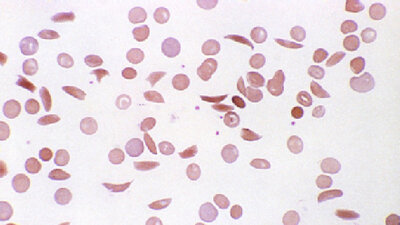

Sichelzellkrankheit: Symptome, Diagnose und Behandlung

Die Sichelzellkrankheit entsteht durch eine ererbte Veränderung des roten Blutfarbstoffs (Hämoglobin). Ihren Namen hat sie von sichelförmig verformten roten Blutkörperchen zum Artikel

Thalassämie

Die Thalassämie ist eine genetisch bedingte Blutarmut. Ein Fehler im Eiweiß Hämoglobin stört den Sauerstofftransport im Körper zum Artikel

Eisenmangelanämie

Eine Eisenmangelanämie ist eine Blutarmut, bei der die Ursache eine gestörte Bildung des roten Blutfarbstoffes Hämoglobin durch einen Mangel an Eisen ist. Erfahren Sie mehr über Symptome, Diagnose und Therapie zum Artikel